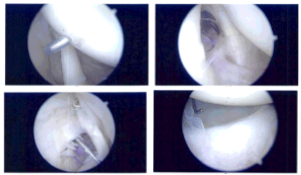

Intraoperative Arthroscopic Images